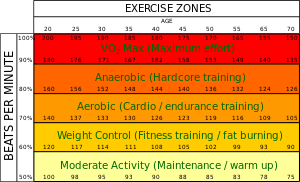

ويناقش هذا القسم معدلات ضربات القلب المرجوة للأشخاص الأصحاء، والتي تكون مرتفعة بشكل غير مناسب لمعظم الأشخاص الذين يعانون من مرض الشريان التاجي.[10]

سرعة القلب المرجوة

بالنسبة للأشخاص الأصحاء، فإن معدل ضربات القلب المستهدف هو المعدل المطلوب التوصل إليه أثناء التمارين الرياضية الذي يمّكِن القلب والرئتين من الحصول على أقصى استفادة من التمرين. ويختلف هذا النطاق النظري باختلاف العمر؛ ومع ذلك، يتم استخدام الحالة البدنية للشخص، والجنس، والتدريب السابق أيضا في الحساب. وفيما يلي طريقتان لحساب سرعة القلب المستهدفة للفرد. في كل من هذه الطرق، هناك عنصر يسمى "القوة" الذي يتم التعبير عنه كنسبة مئوية. يمكن حساب سرعة القلب كنطاق من 65-85٪ في القوة. ومع ذلك، فمن الأهمية بمكان استخلاص أقصى معدل لضربات القلب بدقة لضمان أن تكون هذه الحسابات ذات مغزى.

على سبيل المثال: شخص أقصى معدل لضربات قلبة 180 (عمره 40 عام، بحساب أقصى معدل لضربات القلب عن طريق 220 - العمر):

- 65٪ من القوة: (220 - (العمر = 40)) × 0.65 ← 117 نبضة في الدقيقة

- 85٪ من القوة: (220 - (العمر = 40)) × 0.85 ← 153 نبضة في الدقيقة

طريقة كارفونين

العوامل التي تتوقف عليها طريقة كارفونين لحساب معدل ضربات القلب المستهدف، وذلك باستخدام نطاق من القوة يتراوح من 50-85٪:[16]

- THR = ((HRmax − HRrest) × % intensity) + HRrest

- حيث THR= معدل ضربات القلب المستهدف

- HRmax= أقصى معدل لضربات القلب

- HRrest= معدل ضربات القلب وقت الراحة

- intensity= القوة

مثال لشخص HRmax= 180، HRrest= 70

- 50% من القوة: ((180 - 70) × 0.50) + 70 = 125 نبضة في الدقيقة

- 85% من القوة: ((180 - 70) × 0.85) + 70 = 163 نبضة في الدقيقة

طريقة زولادز

طريقة زولادز هي بديل لطريقة كارفونين، وتستخلص مناطق الممارسة بطرح قيم من أقصى معدل لضربات القلب:

- THR = HRmax − Adjuster ± 5 bpm

- حيث THR= معدل ضربات القلب المستهدف

- HRmax= أقصى معدل لضربات القلب

- Adjuster: الضابط

- منطقة الضابط1 = 50 نبضة في الدقيقة

- منطقة الضابط 2= 40 نبضة في الدقيقة

- منطقة الضابط 3= 30 نبضة في الدقيقة

- منطقة الضابط 4= 20 نبضة في الدقيقة

- منطقة الضابط 5 = 10 نبضات في الدقيقة

على سبيل المثال: شخص HRmax= 180:

- المنطقة 1 (تمارين سهلة): 180 - 50 ± 5 ← 125 - 135 نبضة في الدقيقة

- المنطقة 4 (تمارين صعبة): 180 - 20 ± 5 ← 155 - 165 نبضة في الدقيقة